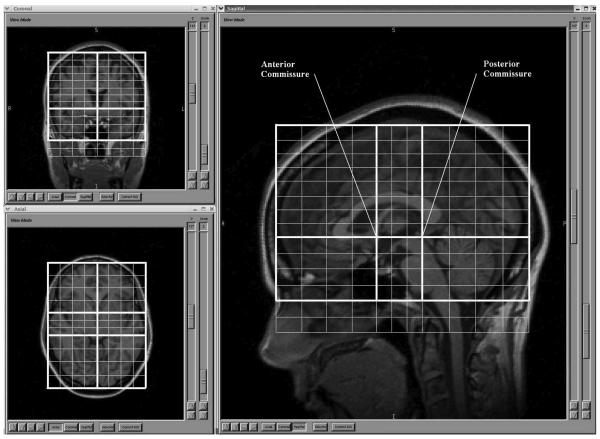

Magnetic resonance images were processed on Linux workstations using the BRAINS2 software package, which is developed and made available by the Mental Health – Clinical Research Center at the University of Iowa.26 BRAINS2 provides an approach for automatic parcellation of the major lobes of the brain, based on the Talairach coordinate system. In contrast to morphometric techniques such as VBM, each participant's brain is analyzed in its native space. This technique involves applying the Talairach coordinate system to each subjects' brain, based on the location of the anterior and posterior commissures, as well as the gross height, width and length.26 Regions of the Talairach grid are pre-assigned by the program to correspond to the major lobes of the brain, and so the lobes in each person's brain are identified based on the its location within the applied Talairach grid. The accuracy of this lobar parcellation method for measuring the targeted lobar volumes has been established by the developers using hand tracing as the gold standard26,35 and numerous studies have used this program to examine volume changes in the brain.27-34 Details of BRAINS2 processing are as follows.

First, the T1 weighted images are resampled to 1.0 mm3 voxels and reoriented so that the anterior-posterior axis of the brain is realigned parallel to the anterior commissure-posterior commissure line and the inter-hemispheric fissure is aligned on the other two axes. Next, the outermost boundaries of the cortex, as well as the anterior commissure and posterior commissure, are identified in order to warp the Talairach grid36 onto the current brain. The T2 and PD weighted images are then realigned to the spatially normalized T1 weighted image using an automated image registration program.37

Intracranial tissue is then classified into gray matter, white matter and CSF in order to identify brain vs. non-brain tissue, using information form the T1, T2 and PD images. This is accomplished using the co registered images and a discriminate analysis method based on automated training class selection,38 which uses a Bayesian classifier approach based on discriminate analysis in order to reduce the variability in signal intensity across individual image sets and to correct for partial voluming. This step requires the manual tracing of venous blood, but is able to perform “plug” selection for grey matter, white matter, and cerebrospinal fluid automatically. The brain mask is then generated using a previously trained artificial neural network (ANN), one of the features of the BRAINS2 software package. Then, lobar volumes are calculated using the validated, automated Talairach-based method of regional classification (see Figure 1).26,35 Tissue classification is visually checked. Because gray-white differentiation was not always accurate, and to increase the generalizability of the study, analyses for this study used whole lobes, including both grey and white matter. Final lobar identification by BRAINS2 was also visually inspected for each case. Major inaccuracy in lobar identification was not identified in any case, and there was no evidence of a systematic problem with lobar identification in any diagnostic group.

Figure 1. Talaraich Parameters of Regional Classification.

This figure illustrates the automated Talairach-based method of regional classification.